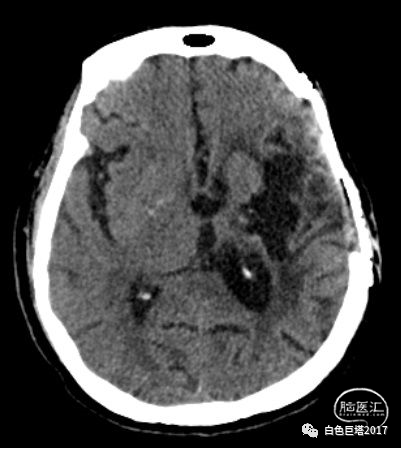

另一例患者苏某,女性, 53岁,因“反复发作意识障碍伴肢体抽搐1天”入住内科。患者既往6年前曾因左基底节区出血行开颅手术治疗。术后遗留右侧偏身感觉、运动障碍,语言功能障碍。6年间多次发生脑缺血性卒中事件、症状性癫痫。

本次入院查体:神志清,运动性失语,定向、理解力正常。双瞳孔等大等圆,直径3mm,对光反射灵敏。双侧咀嚼肌有力,张口无偏斜,面部感觉对称无减退,双侧角膜反射存在。双额纹对称,眼睑无下垂,闭合有力,右侧鼻唇沟浅,示齿口角向左偏斜。粗测听力大致正常。双软腭上抬好,悬雍垂居中,咽反射存在,伸舌偏右。右侧肢体肌张力增高,左上肢肌力5级,左下肢肌力0级,右上肢肌力2级,右下肢肌力1级。双下肢腹股沟以下感觉消失。腹壁反射消失。双下肢深反射稍亢进。双侧锥体束征(+)。脑膜刺激征阴性。

考虑患者体格检查结果与既往病史不符合,患者语言功能障碍,不能很好配合检查。请我科会诊,急诊完善胸腰椎磁共振平扫+增强。

图示:T1

图示:T2,红色箭头所示T10-T12水平椎管内硬脊膜外低信号。

图示:T2压脂像,T8椎体血管瘤。

T2水平面可见相应节段脊髓明显受压。